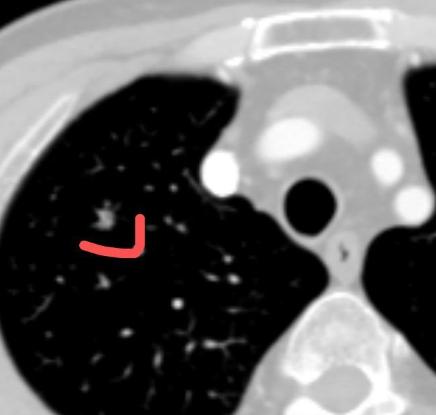

门诊一位患者肺结节术后是肺浸润癌1A1期,肿瘤小于1cm,术后6年右肺下叶“新发”小结节,没有写实性和磨玻璃,大小4毫米、边界清晰,很担心会不会是复发了? 我的回答是:请放心!从大概率上讲,这种微小结节首先考虑是良性的。 您之前是1A1期肺癌,肿瘤小于1厘米,术后又已经超过了5年这个关键时间点,这本身就是一个非常积极的信号,说明之前的治疗应该是治好了,总体上是问题不大的。 所以,对于这个新出现的4毫米结节,我们首先考虑它是良性的炎症结节。您不必为此过度紧张。 其实,我们每个人的肺部都可能出现这种情况。我经常和患者打比方:我们每时每刻的呼吸,空气里都存在细菌、病毒。 当肺部发生一次非常轻微、您自己都完全感觉不到的局部炎症时,身体免疫力在修复过程中,就可能形成一个这样的小结节。 可以说,很多人肺里都可能有过类似的小影子,只是绝大多数人没有进行像您这样精密的CT检查,所以没有被发现而已。 等过一段时间,身体正常的免疫力把这个小小的炎症灶吸收掉,它自然也就消失了。 因此,给这个结节一点时间,也给您身体的自我修复一点时间,建议半年后回来复查一次就可以了。[作揖][玫瑰]胸外科乔贵宾医生肺结节[超话]